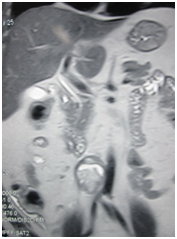

Complete hemogram, liver and renal function tests were within normal limits, normal electrocardiograph and normal chest radiograph. His abdominal x-ray and ultrasound examinations were with no abnormality detected. Urinary 24 hours vanillyl mandelic acid was elevated (18mg/day against 2-8 mg/day). His chest CT was normal. MRI abdomen and pelvis showed a well-defined, heterogeneously enhancing retroperitoneal mass lesion seen beyond the aortic bifurcation at the level of the right common iliac artery abutting the common iliac artery and the IVC with areas of flow voids. Other solid organs normal patient diagnosed extra adrenal pheochromocytoma (paraganglioma). Put on alpha blocker- prazocin 1mg and enalapril 5 mg. Beta blockers were withheld as the patient’s pulse & BP standardized on Alpha blockers itself. Patient was taken up for laparotomy for excision of the tumor. Trans peritoneal approach was followed.

Figure 2 MRI abdomen coronal- paraganglioma near aortic bifurcation.